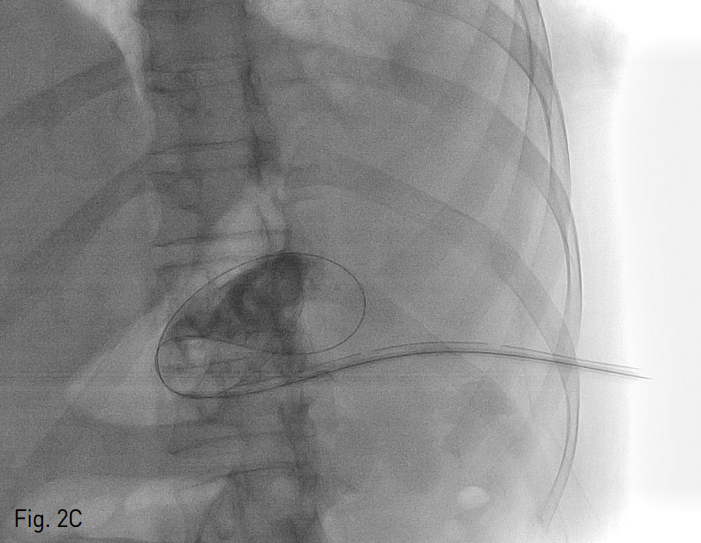

Fig. 2

Contrast accumulation through 5 Fr yellow sheath insertion after ultrasonograhy guided 22-gauge Chiba needle puncture (A). Up to 18 Fr rigid dilator was advanced coaxially over the 0.035 inch hydrophilic guide wire, progressively (B). 18 Fr Thal-Quick chest tube (Cook, Bloomington, IN, USA) was placed (C). The final catheter position can be confir med radiographically with contrast material (D).